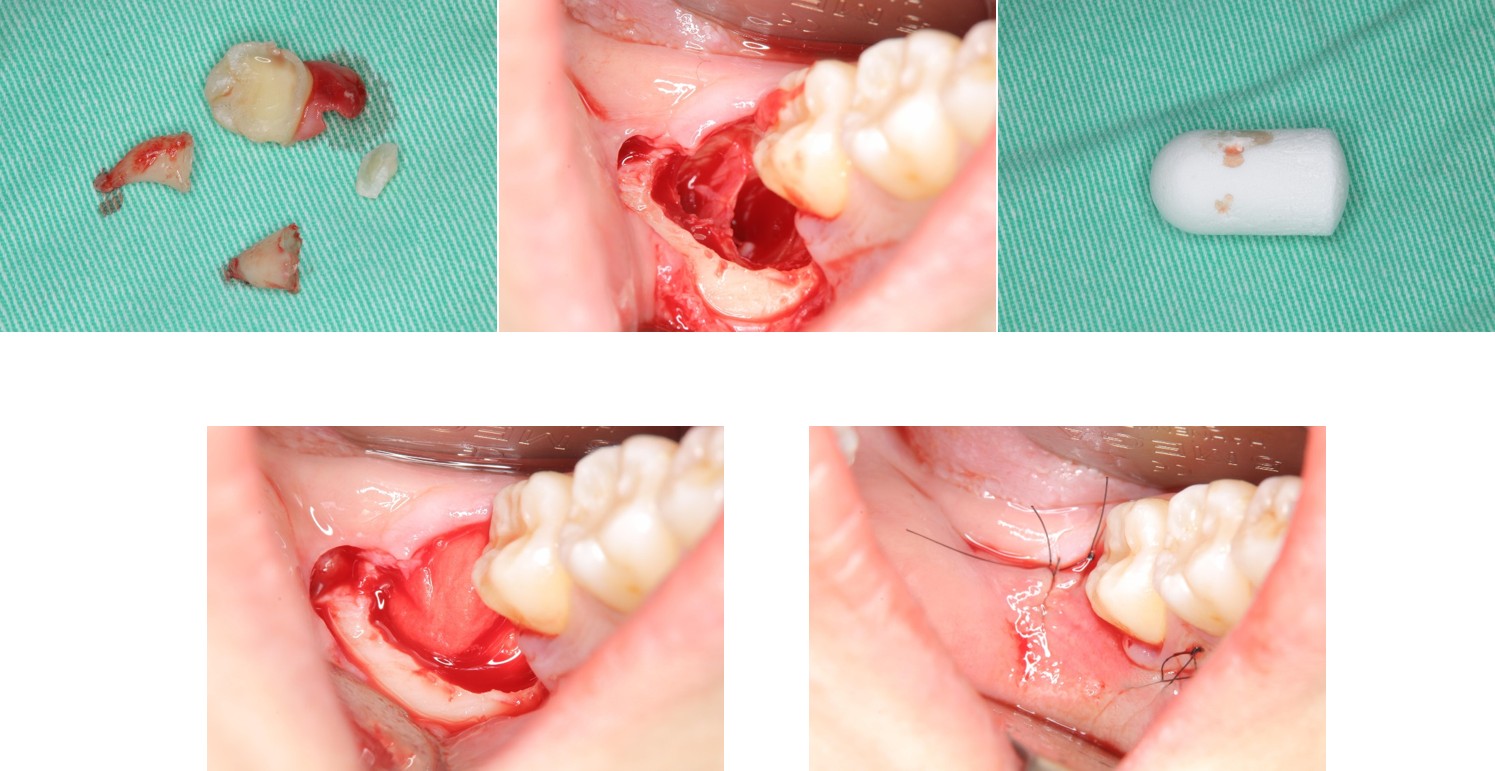

以水雷射切割皮瓣止血、再以手機等拔除阻生齒,並縫合之

1週後傷口癒合良好

使用骨質增生膠原蛋白,來處理拔牙後的傷口。此材料適用的範圍不僅用於拔牙後傷口,所有顎骨中的病灶於手術後皆建議使用。

因此在拔牙後的傷口如果可合併骨原修復傷口,對傷口癒合,有相當的幫助。